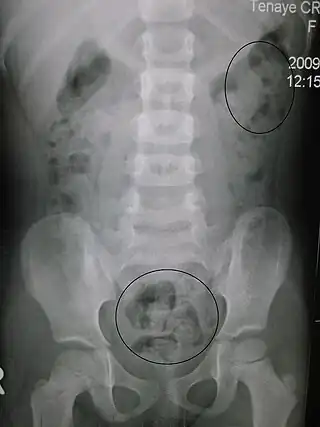

Estreñimiento visto a través de rayos X. Los círculos representan áreas de materia fecal (las heces están rodeadas de blanco debido al gas de los intestinos).

Las radiografías del abdomen, por lo general solo se realizan si se sospecha obstrucción intestinal que puede revelar materia fecal retenida en el colon, y confirmar o descartar otras causas de síntomas similares.